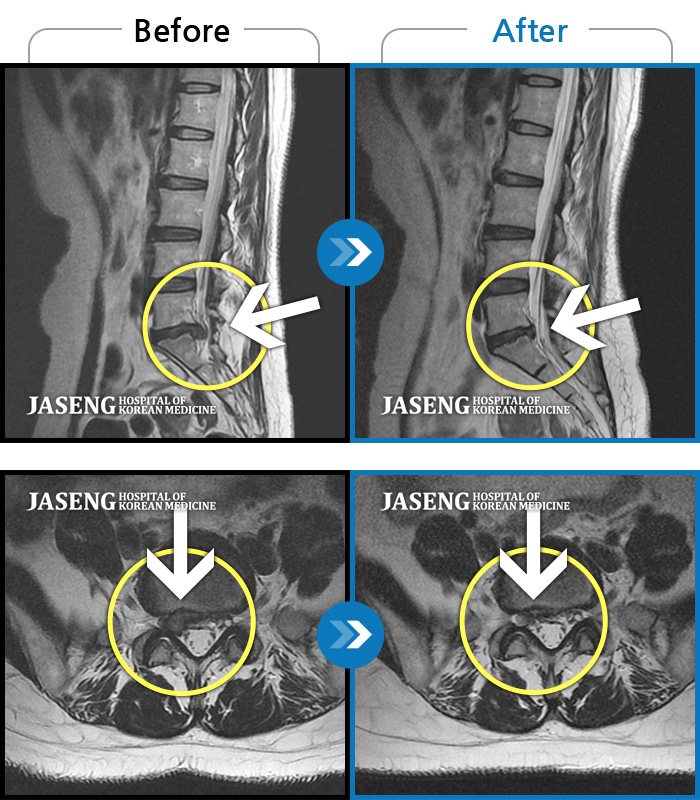

허리 골반 통증이 있고 다리가 저리고 아파 걷기가 힘들다.

2025.02.10 ~ 2025.09.13